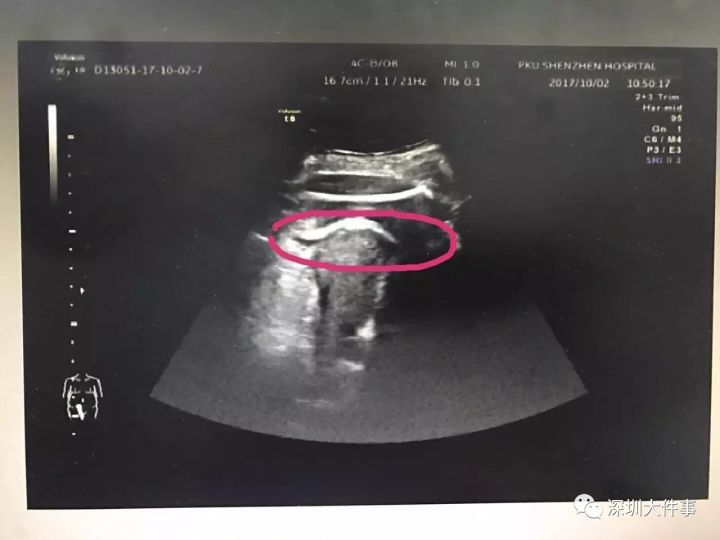

在B超室,医生检查发现孕妇腹腔大量积液,而且在宫前壁近宫底处,胎儿股骨回声在子宫肌层以外,患者该处触痛也非常明显,肝肾间隙积液明显。

“虽然没有找到子宫的破裂口,但通过B超可以看到,在孕妇腹部最疼的地方,先看到的是孕妇的皮下脂肪,然后看到的是胎儿的腿,最后才看到孕妇子宫。胎儿的腿已经‘冲破’了子宫进入腹腔,大腿根正卡在子宫壁上。”专家告诉记者。

▲红色圆圈处是胎儿的腿,已经伸到子宫壁外